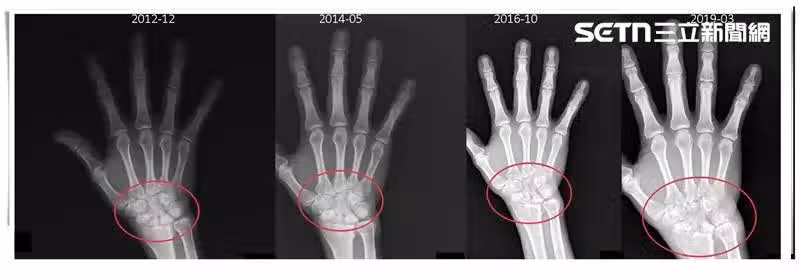

黃柏豪指出,以張先生為例,他的發炎指數雖正常,但手部關節內部悄悄被破壞,這種「骨侵蝕」是不可逆的情形,若置之不理,最後甚至可能會造成手部變形、無法正常握持工具,嚴重影響生活與工作品質,經比對患者近年來的X光檢查影像,發現確實已經出現異常,於是改用另款新型生物製劑治療後,關節破壞程度才穩定放緩,目前已經恢復原本生活步調。